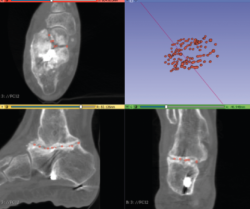

Figura 1. Fractura conminuta de la cúpula del astrágalo.

Se trata de un paciente varón de 35 años que, tras una precipitación, presenta impotencia funcional en el miembro inferior. Tras la valoración clínica y radiológica, se observa un estallido de la parte posterior de la cúpula astragalina (Figura 1).

- Obtención de la forma real del defecto combinando el astrágalo con una imagen especular del astrágalo contralateral (Figura 2).